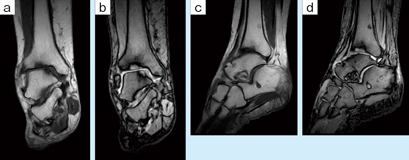

■症例3:変形性足関節症

74歳,女性。足関節の痛みを訴え受診。単純X線では,関節裂隙がやや内側で狭少化している程度であった。MRIにて,脛骨,距骨とも荷重部に一致した骨軟骨壊死を認め,痛みの原因と診断した。 a:T1WI,COR,FOV:200mm,TR/TE:400/26,FA:90°,スライス厚:3mm b:T2*WI,COR,FOV:200mm,TR/TE:660/13.5,FA:30°,スライス厚:3mm c:T1WI,SAG,FOV:200mm,TR/TE:400/26,FA:90°,スライス厚:3mm d:T2*WI,SAG,FOV:200mm,TR/TE:660/13.5,FA:30°,スライス厚:3mm